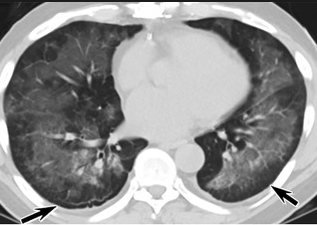

怎么“中度可疑”呢?这些专家表示,这5位患者的肺部CT都具备新冠肺炎CT的影像特征,比如肺部出现磨玻璃的影像,磨玻璃主要分布在双下肺靠近外周,出现铺路石征、严重的表现为双肺弥漫性多发实变。同时,其病程转归和临床特征也与新冠肺炎相似。

以下面这4张图涉及的这个美国“电子烟”病人为例,专家不是仅仅通过一张影片做判断的,而是通过这4张涵盖了这名病例肺部多天变化情况的影片进行的研判,认为该病例的病程进展跟新冠更为相似。